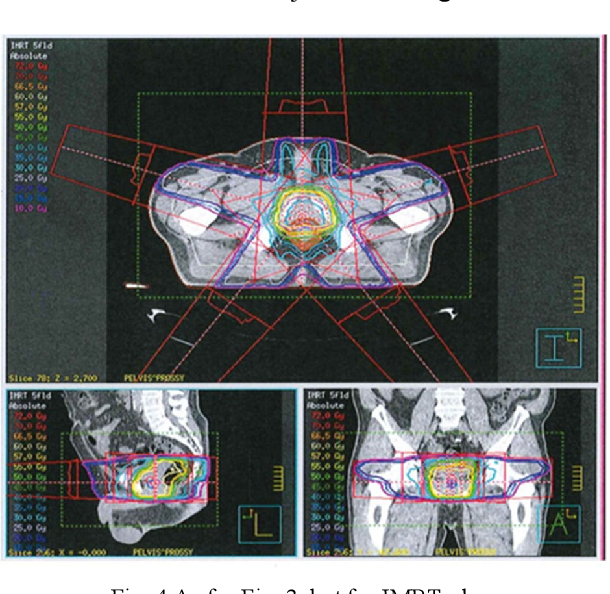

what treatment type is this

IMRT